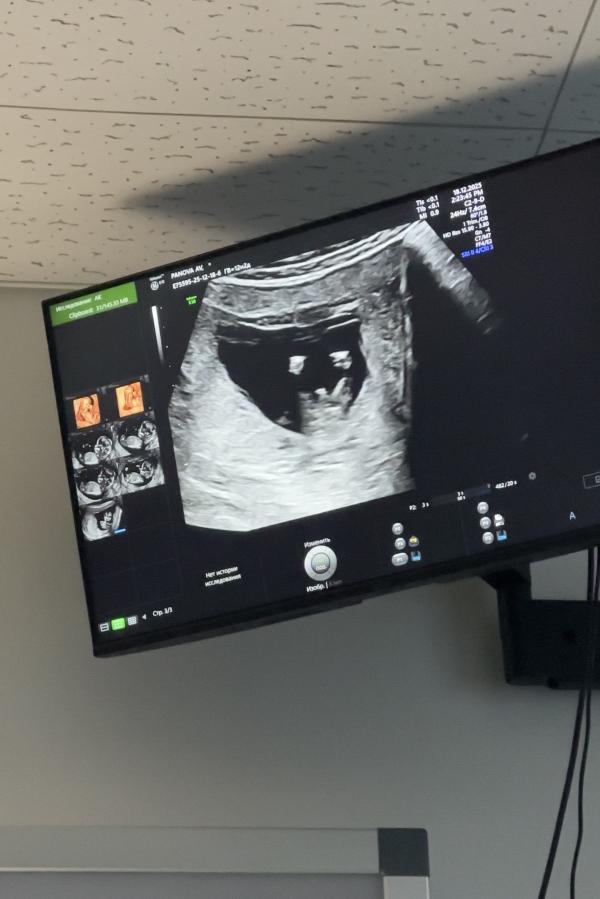

После этой ужасной жк №1 и Ивановой. Наревелась и поехала в «Саико», несмотря на то что там была полная запись и некоторые специалисты на больничном меня согласилась взять глав-врач Щетнева Ольга Александровна. Сделали фетометрию. Какая же замечательная женщина, все показала, рассказала, я в кабинете была наверно минут 40 если не больше, пыталась подлезть, повернуть малыша, разбудить чтоб сфотографировать. Я сняла все на видео, увидела ручки, ножки, пальчики. И даже пол смогли увидеть да так отчетливо что просто без сомнений.

У нас будет мальчик🩵